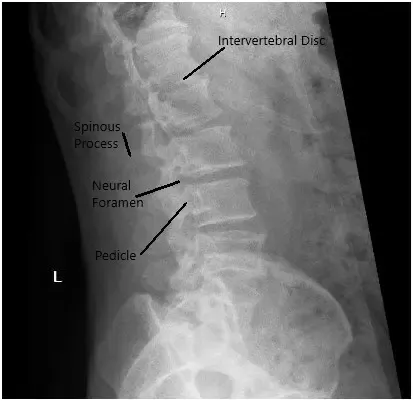

La radiografía en vistas AP y laterales mostró el estrechamiento del disco L5-S1